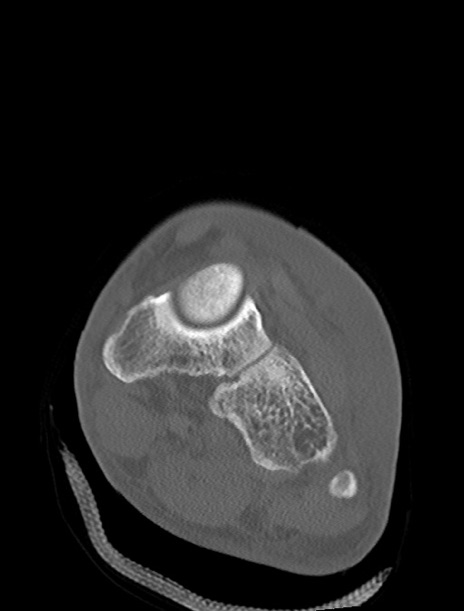

左足関節CT

横断像